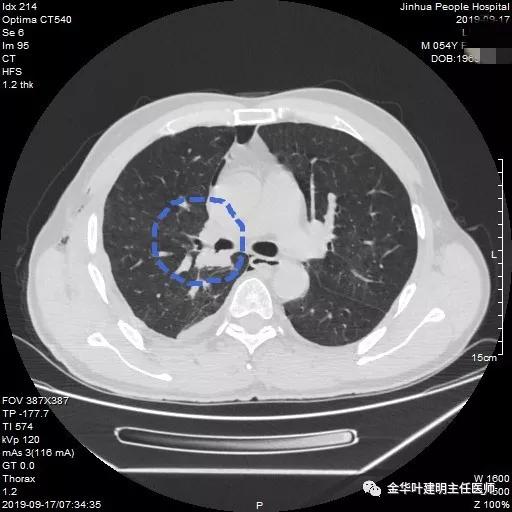

可见右中间支气管开口处新生物,堵塞管腔,明显是肿瘤,但因当时服用波立维与阿斯匹林双抗治疗,停的时间还不够,所以没有活检,而刷检没找到癌细胞。请我会诊时,我看了李某的胸部CT增强:

上图示上叶支气管通畅

上图示中间支气管起始处似乎还算正常

上图示中间支气管起始处以下3毫米处已经管壁增厚异常

上图示肿瘤堵塞管腔

上面各图示肿瘤位于肺门部,堵塞下叶及中间支气管

我们仔细看了增强CT,纵隔未见确切疑似转移的肿大淋巴结,这样的情况下,是不是再次气管镜活检,还是直接可以手术?当然从原则上来讲,应该再重新纤支镜检查,再活检以取得病理确诊后,再行手术。但个人以为,从影像及气管镜所见来讲,临床诊断已经可以确定为肺癌,而且中央型的以鳞癌为多见,当然也有的会是小细胞癌,不过小细胞癌一般很早就会有纵隔淋巴结转移,如果患者及家属理解,我认为从减少痛苦、节约经费、节省时间等方面考虑,直接手术也基本不会错的。当然所有的利弊与可能都要如实与患者及家属沟通,并征求他们的意见,最终李某及家属选择不再重新纤支镜检查与活检,要求直接手术。